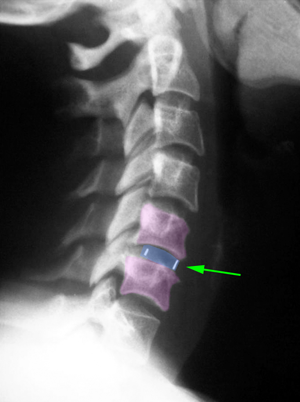

Περιγραφή Η έκταση της σπονδυλοδεσίας και ο τρόπος με τον οποίο πραγματοποιείται εξαρτώνται από το είδος και το μέγεθος της βλάβης που πρέπει να αναταχθεί. Στην εκφυλιστική νόσο προηγείται της σπονδυλοδεσίας η αυχενική δισκεκτομή, σε ένα ή περισσότερα επίπεδα της αυχενικής μοίρας της σπονδυλικής στήλης. Η προσπέλαση είναι όμοια. Στη θέση του δίσκου(-ων) που αφαιρούνται τοποθετείται ένας κλωβός, κατασκευασμένος συνήθως από ειδικό πολυμερές πλαστικό, ο οποίος περιέχει στο κέντρο του οστικό μόσχευμα. Αυτό διατηρεί ή αυξάνει το ύψος του μεσοσπονδυλίου διαστήματος και διανοίγει τα νευρικά τρήματα. Σε ένα ορίζοντα μερικών μηνών στη θέση του οστικού μοσχεύματος δημιουργείται καινούργιο οστό το οποίο συνενώνει τους άνω και κάτω του μοσχεύματος σπονδύλους. Ενισχυτικά της παραπάνω αρθροδεσίας, ιδιαίτερα όταν πρόκειται να αφαιρεθούν παραπάνω τους ενός αυχενικοί δίσκοι, τοποθετείται μια μεταλλική πλάκα στην πρόσθια επιφάνεια των σπονδύλων η οποία στερεώνεται με βίδες σε αυτούς, προκειμένου να επιτευχθεί άμεση σταθεροποίηση. Στην τραυματική αστάθεια του αυχένα η επέμβαση είναι ουσιαστικά ίδια με την διαφορά ότι σε λίγες περιπτώσεις μπορεί να μην απαιτείται δισκεκτομή και η σπονδυλοδεσία να αποτελείται μόνο από την πρόσθια πλάκα και τις βίδες. Στην διάβρωση των σπονδύλων από όγκο, η επέμβαση συμπεριλαμβάνει και την αφαίρεση της χωροκατακτητικής εξεργασίας και αυτό συνήθως συνεπάγεται και αφαίρεση μέρους του σώματος του σπονδύλου. |

Πρόσθια αυχενική δισκεκτομή και σπονδυλοδεσία με κλωβό από PEEK (μπλέ) Α5-Α6. |